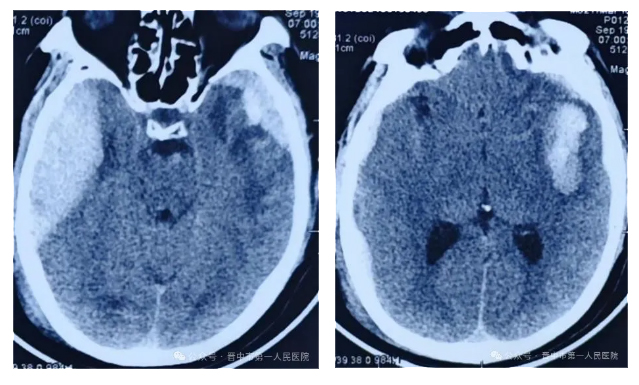

第一次術(shù)前:雙側(cè)顱內(nèi)出血,出血量大

第一次術(shù)后:血腫完全清除